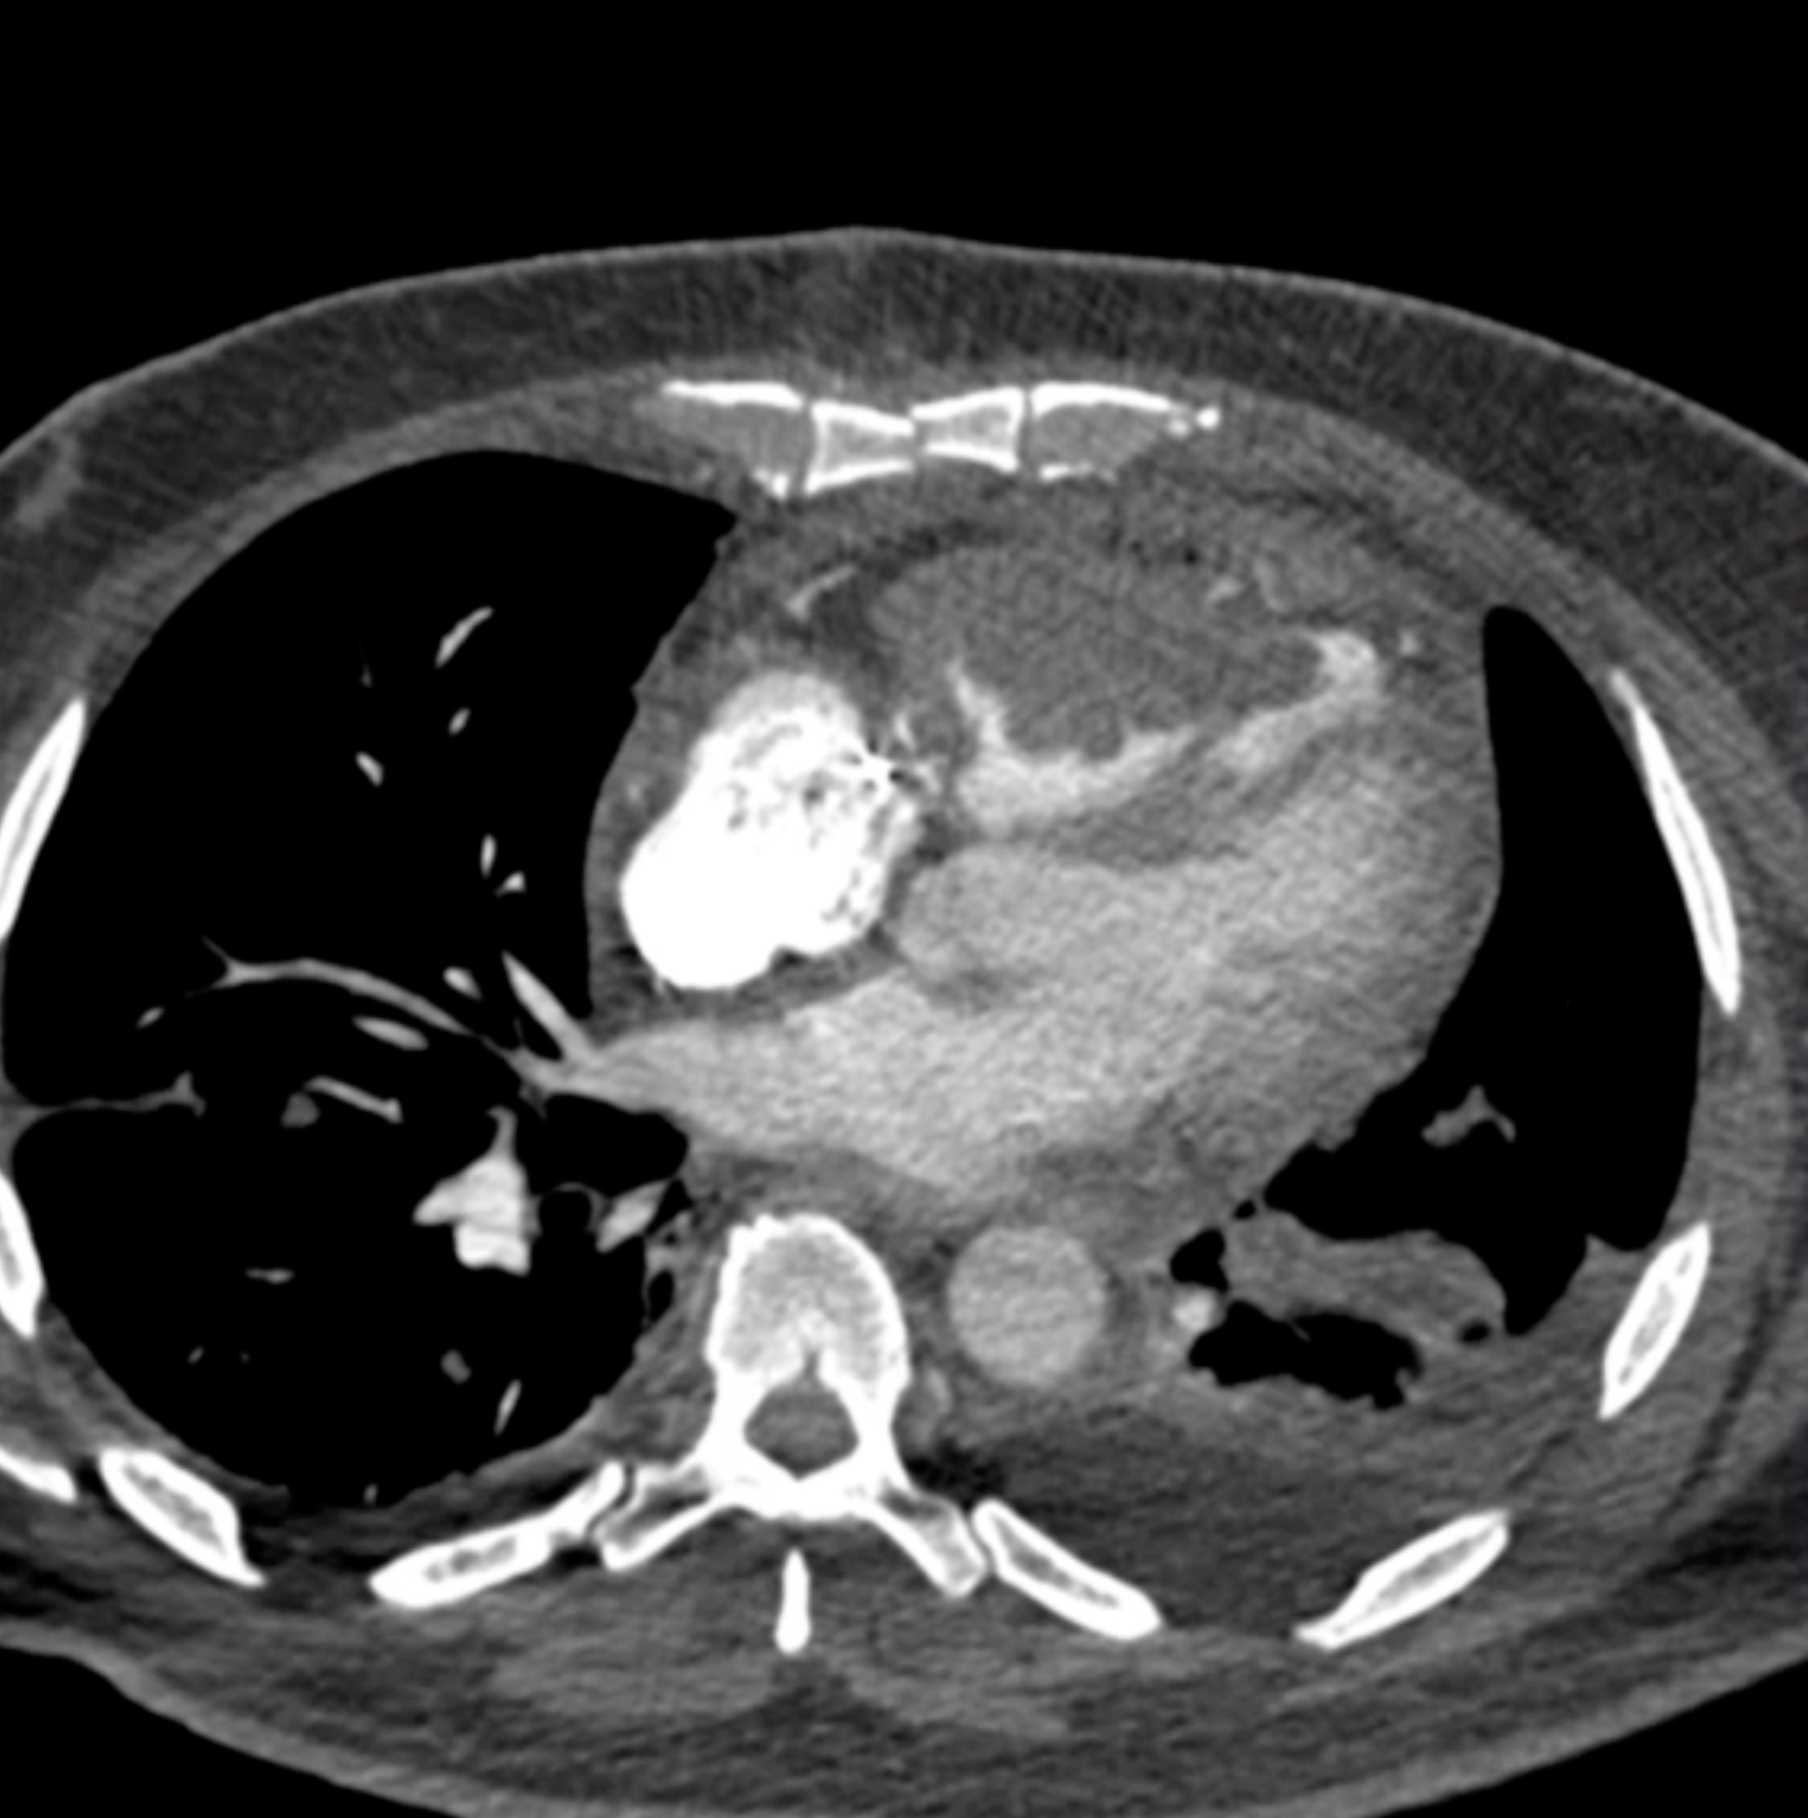

Primary Spindle Cell Carcinoma of the Right Ventricle